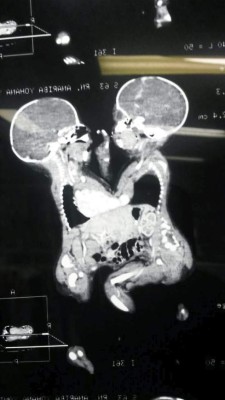

Ayer en horas de la tarde les practicaron otra resonancia, la cual confirmó que ambas comparten un solo corazón y el hígado, dijo el neonatólogo Samuel Santos. Debido a que ambos órganos son importantes, los médicos especialistas no pueden determinar cuánto tiempo más podrán vivir. El caso de las pequeñas sigue siendo de los más complicados porque un solo corazón las mantiene con vida.

Foto: La Prensa

Los médicos presentaron la última resonancia de las niñas.